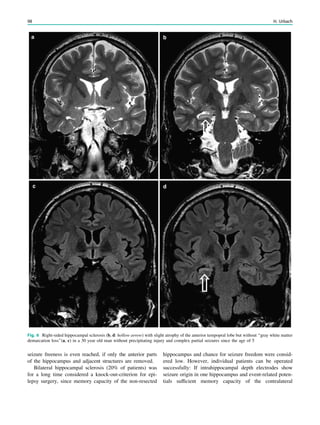

To achieve freedom from seizures following epilepsy

surgery, in some but not all cases not only the epileptogenic

lesion itself but also some perilesional tissue must be

removed. Conceptually, it is the epileptogenic area that has

to be removed, which is defined as cortical area indis-

pensable for the generation of seizures. Practically, it is the